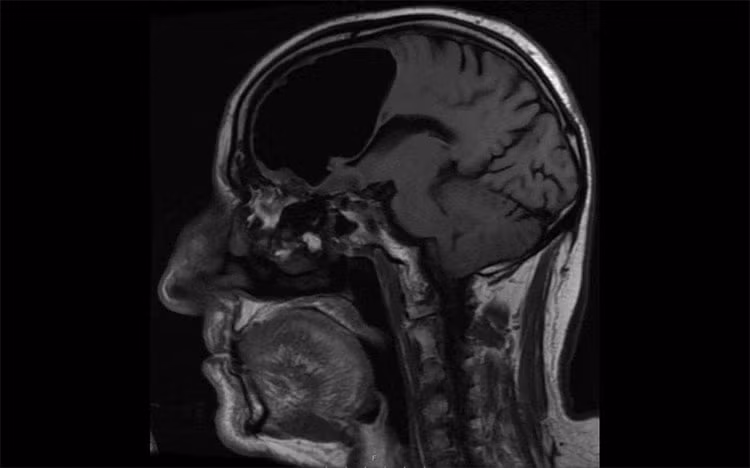

Dự án xây dựng máy MRI mạnh nhất đã được chính phủ phê duyệt với sự cố vấn của giáo sư Zhao Zhongxian. Các máy MRI thông thường hiện nay chỉ có thể tích lũy từ trường dao động khoảng 1,5 - 3 tesla, trong khi cỗ máy mạnh nhất hiện nay tại Mỹ và châu Âu là 11 tesla.

Quá trình thiết kế và phát triển công nghệ có thể tốn nhiều chi phí. Tuy nhiên, công nghệ MRI sau này có thể thay thế hoàn toàn tia X vì không tạo ra phóng xạ, không gây tổn hại cho cơ thể.

Dù vậy, yếu tố an toàn vẫn phải đặt lên hàng đầu, vì chưa có ai từng tiếp xúc với từ trường mạnh tới 14 tesla. Giáo sư Lu Haidong tại ĐH Bắc Kinh nhấn mạnh rằng rủi ro phải được đánh giá cẩn thận trước khi sử dụng trên người sống. Mặc dù dự án còn ở giai đoạn đầu, nó đã gây chú ý lớn và hứa hẹn mang lại những đột phá lớn trong nghiên cứu não bộ.